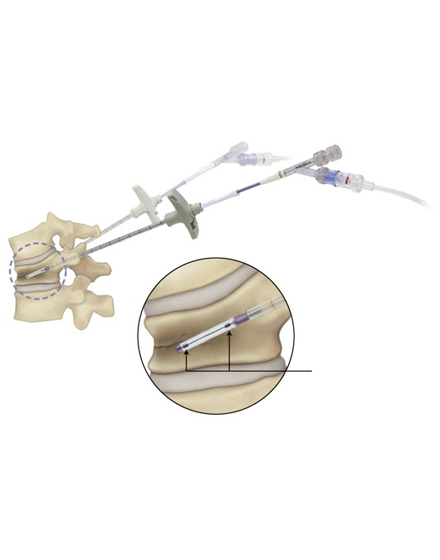

経皮的椎体形成術 BKP(ビーケーピー)

適応となる疾患:骨粗鬆症性椎体骨折、転移性脊椎腫瘍

骨粗鬆症による背骨の骨折や転移性脊椎腫瘍(がんの背骨への転移)による病的骨折に対して世界中で行われている低侵襲な手術法です。日本では2011年に保険適用になり行われています。全身麻酔をして背中の約5mmの傷2カ所から細い針を骨折椎体に挿入します。その針を介して風船(Balloon)を骨折椎体内に設置し、ゆっくりと潰れた骨を整復・復元します。整復後に除去した風船のスペースに骨セメントを注入して、骨折を人工的に接合します。手術は約1時間程度で、手術直後から痛みが軽減することが多く、翌日より起立・歩行を開始します。入院期間は通常約3~7日程度になります。